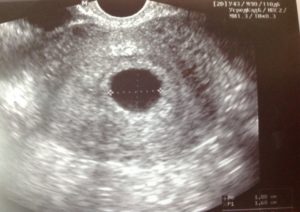

Показатели УЗИ

• Сердцебиение эмбриона не определяется. В норме на ультразвуковом исследовании оно заметно, начиная с 5 недели беременности.

• Плодное яйцо не имеет диаметра таких размеров, которые предполагает срок беременности.

• Величина эмбриона, находящегося в плодном яйце, не соответствует сроку беременности.

• Если срок до 4 недель, то признаком гибели плодного яйца является деформация.

• Эмбрион не визуализируется на сроке 6 – 7 недель.

Признаки замершей беременности, например, на 8 или 10 неделе отчетливо определяются при первом проведении процедуры ультразвукового исследования. Но если срок еще мал, и не превышает 5 недель, то даже аппаратная диагностика способна сделать ошибку: не визуализировать эмбрион или не заметить его сердцебиение.

Поэтому на маленьком сроке при определении погибшей беременности УЗИ всецело доверять нельзя. В таком случае следует прийти через неделю и предпринять новую попытку выявить наличие жизнедеятельности эмбриона.